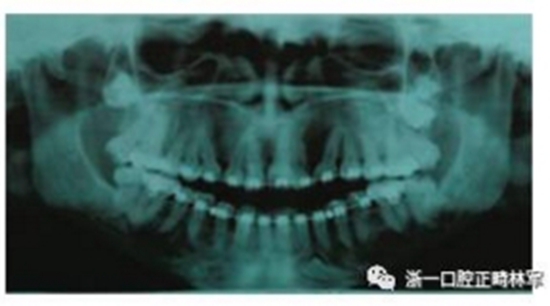

全景片示,上頜第三磨牙未萌,左上頜與左下頜各存在一顆多生牙。頭影測(cè)量數(shù)據(jù)如下。